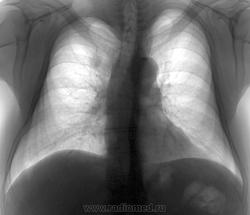

Периферический "хамелеон"

Очередной профосмотр.

Вспомнил вчерашее наблюдение Юлии Игоревны. По прямому весьма похоже, но....

Выкладываю и архив за два предыдущих года. Ваше мнение?